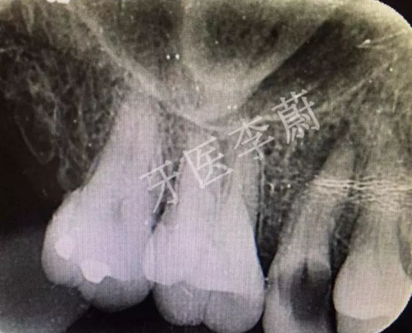

局部X牙片

X片示:15殘冠影,根尖有骨密度降低影。

口腔檢查:15冠部齲損,探及大量腐質(zhì),舌側(cè)冠折至齦下約2mm,近、遠(yuǎn)中壁亦部分齲壞,松動(dòng)Ⅰ°,叩痛(-) ,牙齦無瘺管,舌側(cè)及近中被齦組織覆蓋。